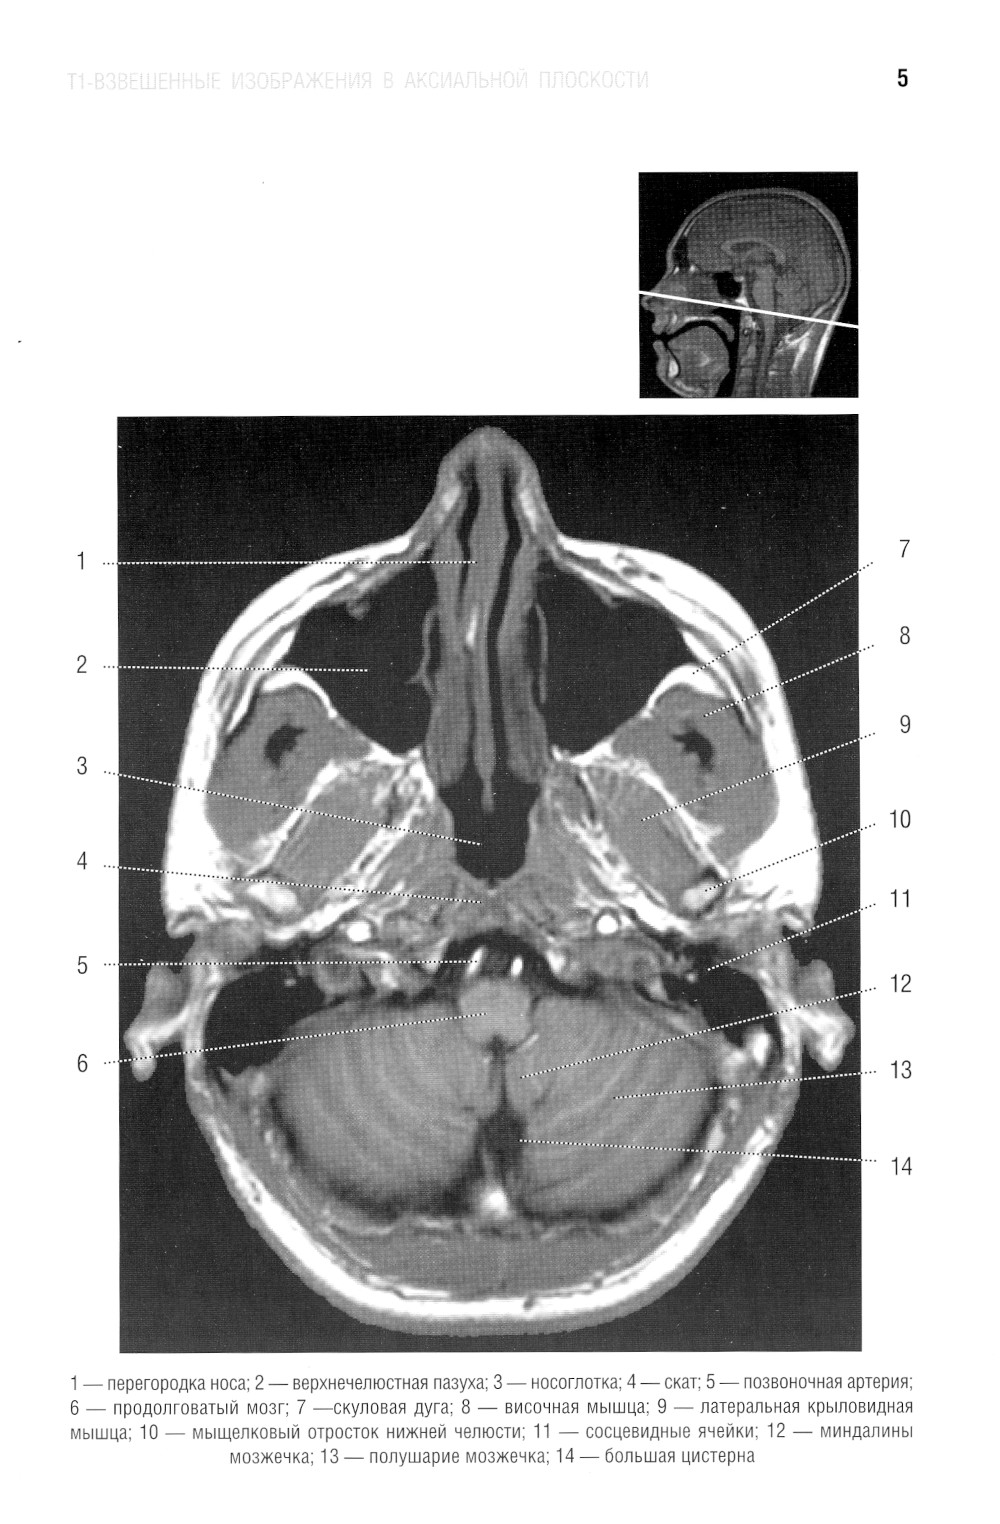

В руководстве представлена нормальная анатомия головного мозга и позвоночника по данным МРТ- и КТ-исследований. MPT-изображения головного мозга отражены в трех взаимно перпендикулярных плоскостях. Отдельная глава посвящена визуализации и нормальной анатомии сосудов головного мозга, в том числе с изображениями, получаемыми при бесконтрастной магнитно-резонансной ангиографии. Для врачей-рентгенологов, специалистов КТ и МРТ, невропатологов, нейрохирургов, а также врачей смежных специальностей. Руководство рекомендовано для обучения студентов медицинских вузов, а также может использоваться в системе последипломного профессионального образования.| Издательство | Элби |